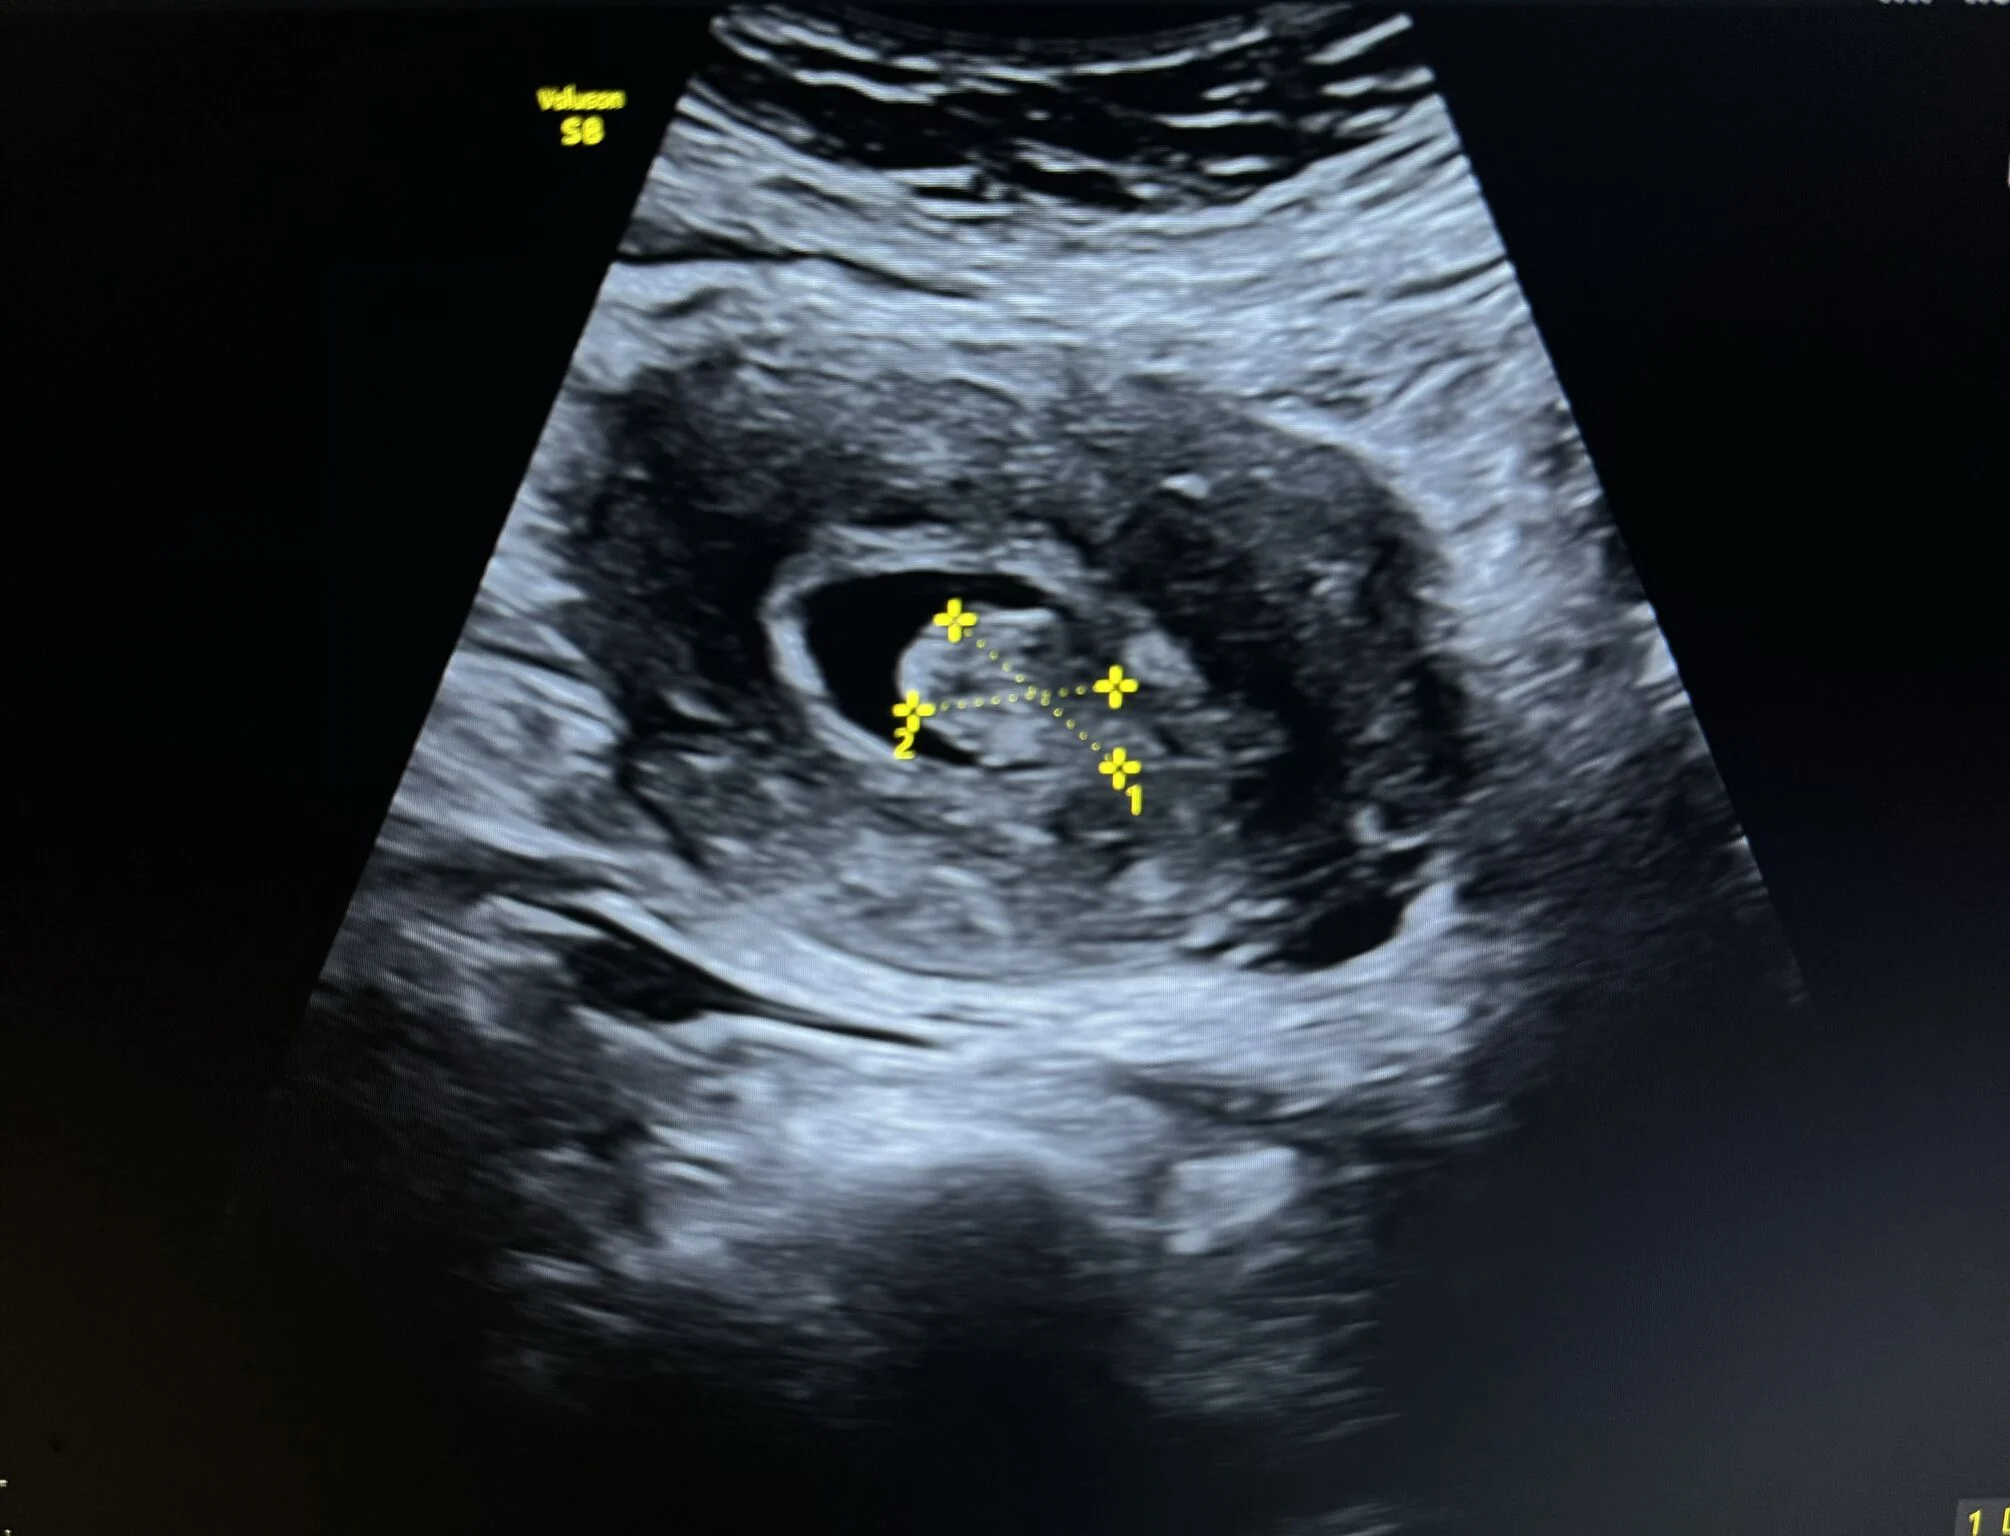

“Case Report: Uterine Polyp

A female patient presented to the clinic with complaints of abnormal uterine bleeding.

Ultrasound examination revealed a large endometrial polyp with notable vascular flow on color Doppler.

Ultrasound Appearance

On ultrasound, an endometrial polyp typically appears as a:

- Well-defined echogenic mass within the endometrial cavity

- Homogeneous texture

- Single central feeding vessel on color Doppler — a key feature distinguishing it from fibroids

Additional features:

- May appear as focal thickening or an oval-shaped lesion

- When using Saline Infusion Sonohysterography (SIS), the polyp can be clearly visualized moving freely within the fluid-filled cavity